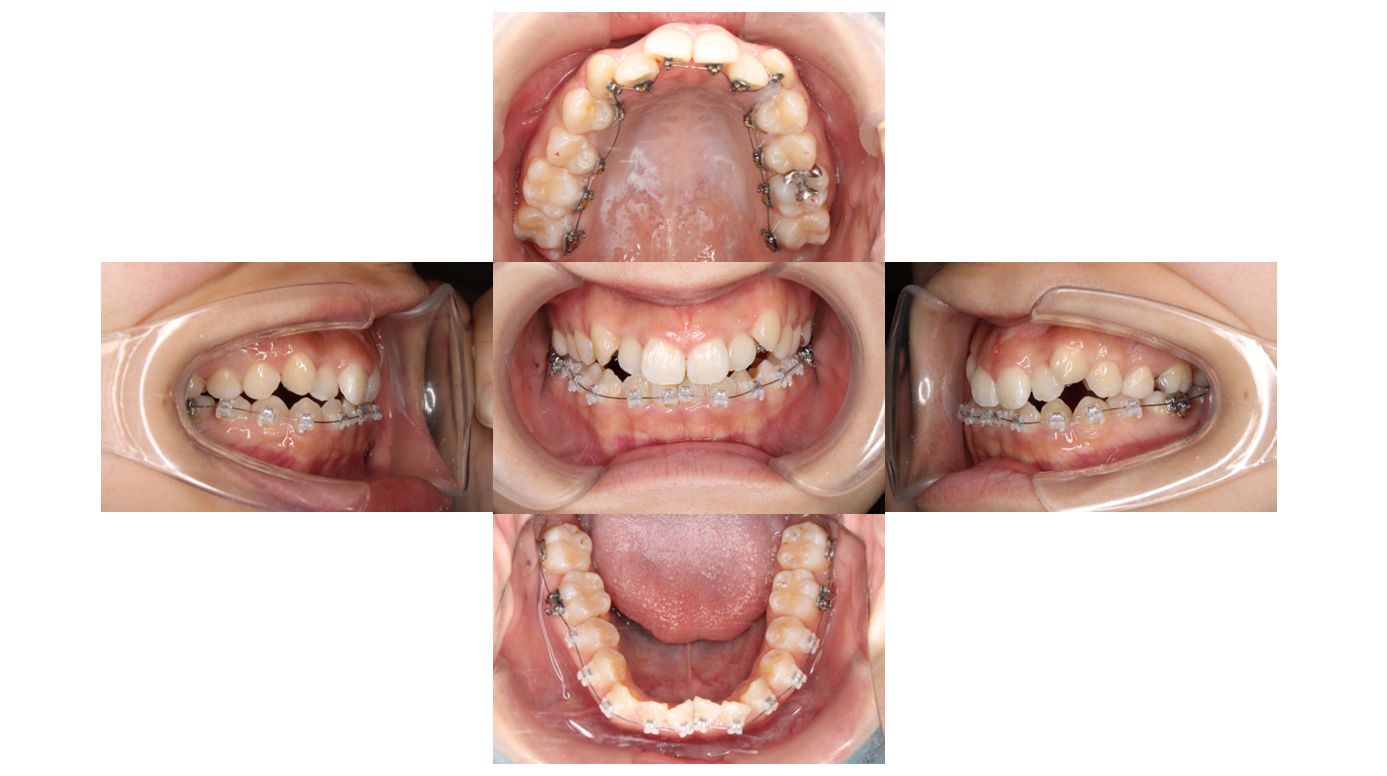

5か月経過

上下ともワイヤーをサイズアップし歯を並べていきます

青い材料は歯と装置が当たらないようにしています